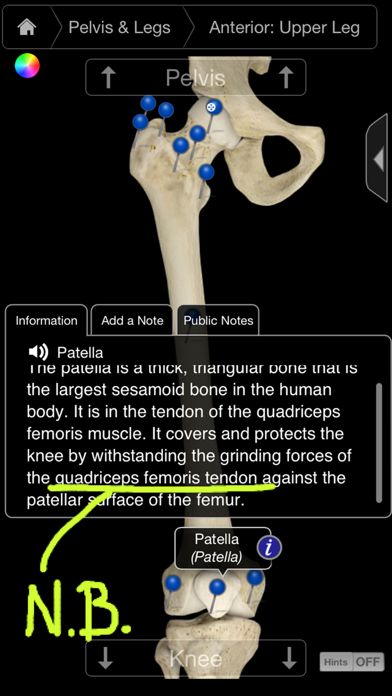

1. Additionally, this app is ideal for physicians, educators or professionals, allowing them to visually show detailed areas of the skeletal system to their patients or students - helping to educate or explain conditions, ailments and injuries.

2. The Skeletal System Pro III - includes the most in depth 3D skeleton ever developed, the ability to rotate, cut and get superior/inferior views all with the simple stroke of the finger.

3. • Double Tap to Zoom - zoom into and identify any region, bone, skeletal area or ligament by tapping on the screen.

4. This app’s primary use is as a learning tool but can also be used as a fast and innovative reference tool by utilizing the index function which allows the user to select an item and the app will automatically zoom in and identify it.

8. • Customize Pins - add your own pins and notes or add notes to existing pins.

9. • Public Notes: Post or browse through shared public notes.